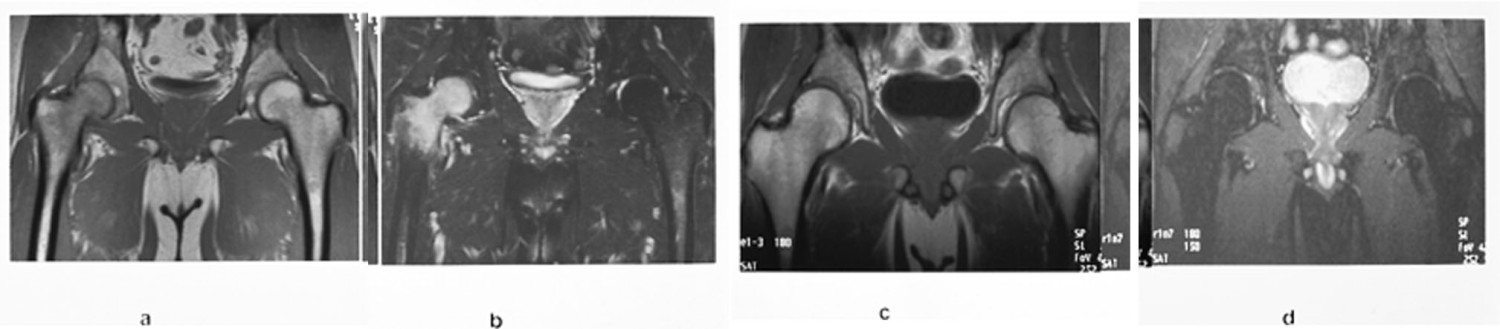

MR-undersøkelse av bekken og hofter blir ofte utført hos pasienter med hoftesmerter hvor konvensjonell røntgen er negativ. MR kan tidlig påvise en osteonekrose og stadieinndele den (fig 13). En klinisk tilstand kjent som beinmargsødem i forbigående osteoporose gir intraktable smerter (10). Dette er en tilstand hvor det er lokalisert osteoporose i caput/collum femoris assosiert med økt væske mellom trabeklene. Røntgenbilder er som oftest normale, spesielt tidlig i forløpet. MR vil vise generelt nedsatt signal på T1-vektet sekvens og betydelig økt signal på STIR-sekvens (fig 14). Tilstanden sees oftest hos middelaldrende menn. Den vedvarer i opptil seks måneder. Årsaken er ukjent.